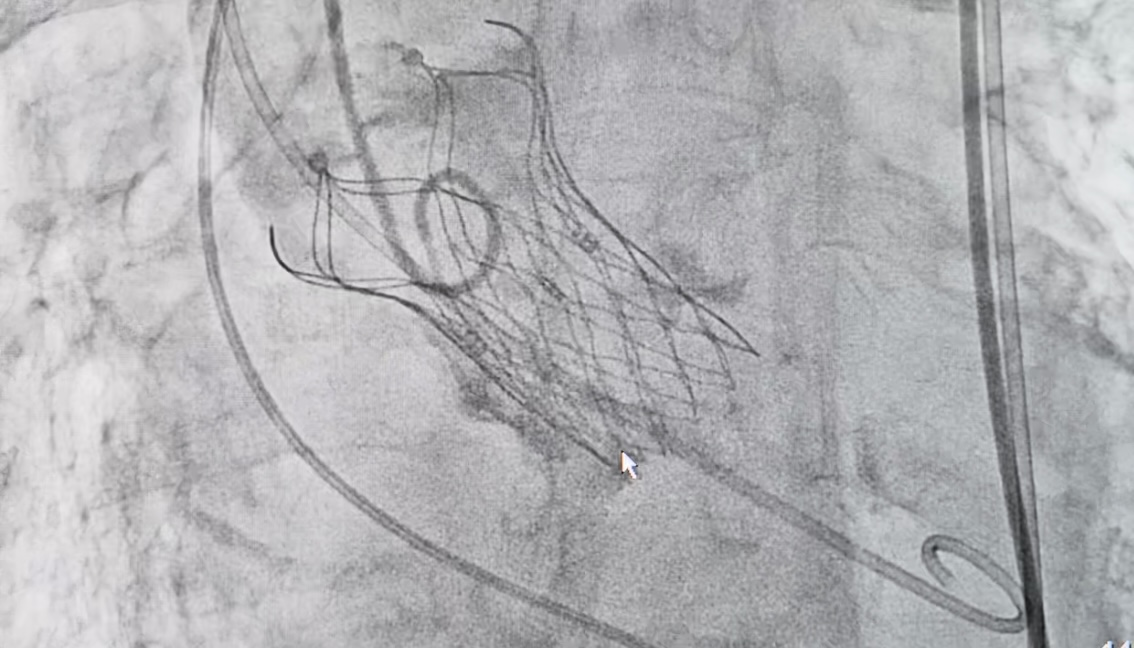

生物瓣膜释放图

术前跨瓣压差146mmHg

术后即可跨瓣压差1mmHg

术前心内科会同手术、麻醉、心超、放射、介入等多个学科专家共同对颜阿婆病情进行深入细致的探讨,制定手术实施方案及制定预案。终于,在我院心内科罗裕,汤勇,帅文欢等专家及多学科老师的共同配合努力下,瓣膜精准释放,跨瓣压差由原来的146mmHg,降低至1mmHg,取得了优异的手术效果。近日颜阿婆已康复出院。